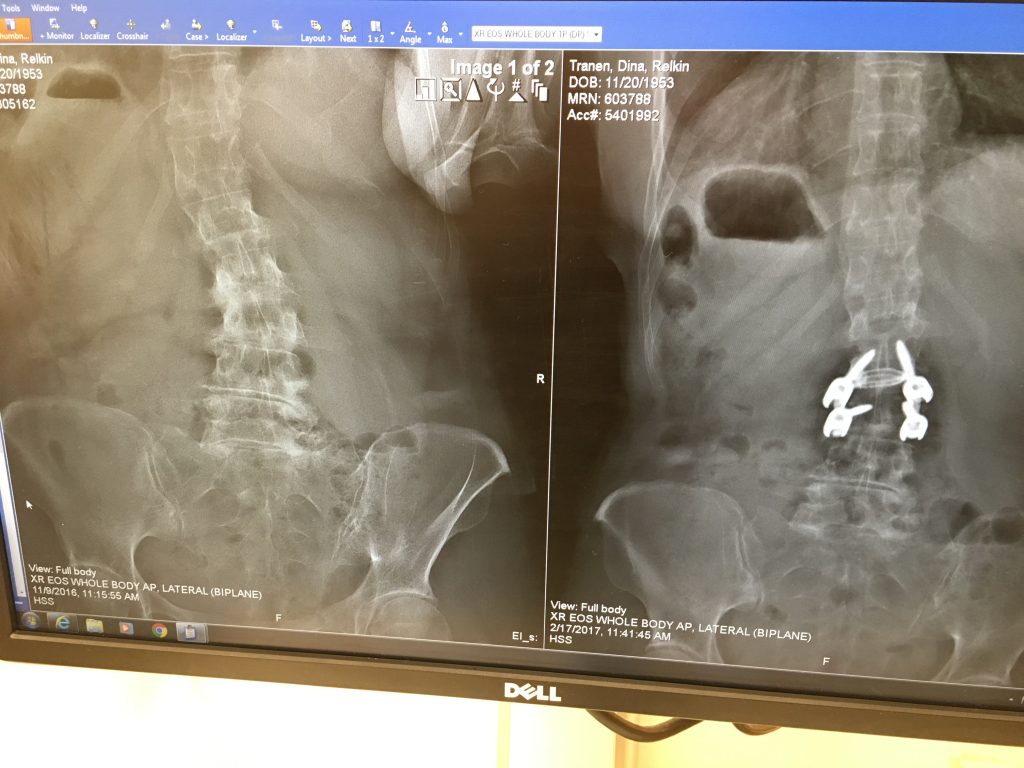

After one year of alternative therapies, including cortisone shots, nerve ablations, physical therapy, etc. to relieve referred pain that I had in my left leg, I was referred to Dr. Schwab. My pain management doctor's "bag of tricks" was in fact empty and I was advised to go forward with surgery. My husband and I interviewed 2 surgeons before we got to Dr. Schwab. At that point, I was scared and not feeling too encouraged. Meeting Dr. Schwab was like seeing a light at the end of a very dark tunnel! His calm and logical analysis totally allayed my fears and made me hopeful that I would actually be free of pain. He explained that he needed to do a fusion, opening my discs and relieving the pressure on the nerve which was clearly crushed. He also explained very clearly what I could and could not do post surgery in order to ensure its success. My surgery was a complete success- I woke up without pain and was walking 4 miles 6 days after my surgery. Not only is Dr. Schwab an incredibly gifted surgeon, he inspires complete confidence. His staff is always available via e mail or phone and the hospital experience was fabulous. I hope I will not need any other "alterations" in the future but if I do, I know who will take care of me!